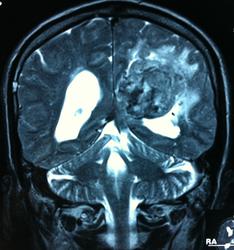

Начало вот здесь http://www.radiomed.ru/cases/kt-gms-obemnoe-obrazovanie-levoi-gemisfery-bolshogo-mozga-vnutrizheludochkovaya-meningioma. Пациент оперирован (меня сначала дезинформировали по поводу операции), перед операцией состояние ухудшилось, возникла правосторонняя гемиплегия, которая осталась и после декомпрессии. МРТ, КТ снимки и выписку предоставила супруга пациента, снимал на iphone, простите за качество, дисков с исследованиями не записывали. Надеюсь вопрос по данному случаю исчерпан.

Вот "цветочки":

T1+C

Т2

FLAIR

И Вы считаете, что эта опухоль имеет интравентрикулярную локализацию?

Изначально по КТ я так предпологал, а теперь на 100% уверен, разве МРТ это не показало? Гистологически - менингиома, опухоль мозговой оболочки. Покажите, пожалуйста, образование где-нибудь прилежит к костям, где есть мозговая оболочка? Я не вижу, зато отчетливо вижу в левом боковом желудочке из оболочек сосудистого сплетения. Что вас еще смущает? По-моему, предостаточно фактов, чтобы развеять все сомнения.

Мне видится так. Иначе в данной локализации просто неоткуда расти оболочечной опухоли. На контрольной КТ, после декомпрессии, когда срединные структуры стали действительно срединны, правое обызвествленное сосудистое сплетение видно отчетливо, а левое, где оно? Ведь если бы образование компремировало, то после операции, когда часть мозга пролабировало в трепанационное отверстие мы бы увидели и левое сосудистое сплетение, но оно интимно связано с образованием и даже "потянулось" за ним в сторону декомпрессионного отверстия, потому что это и есть "росток" откуда выросла опухоль.